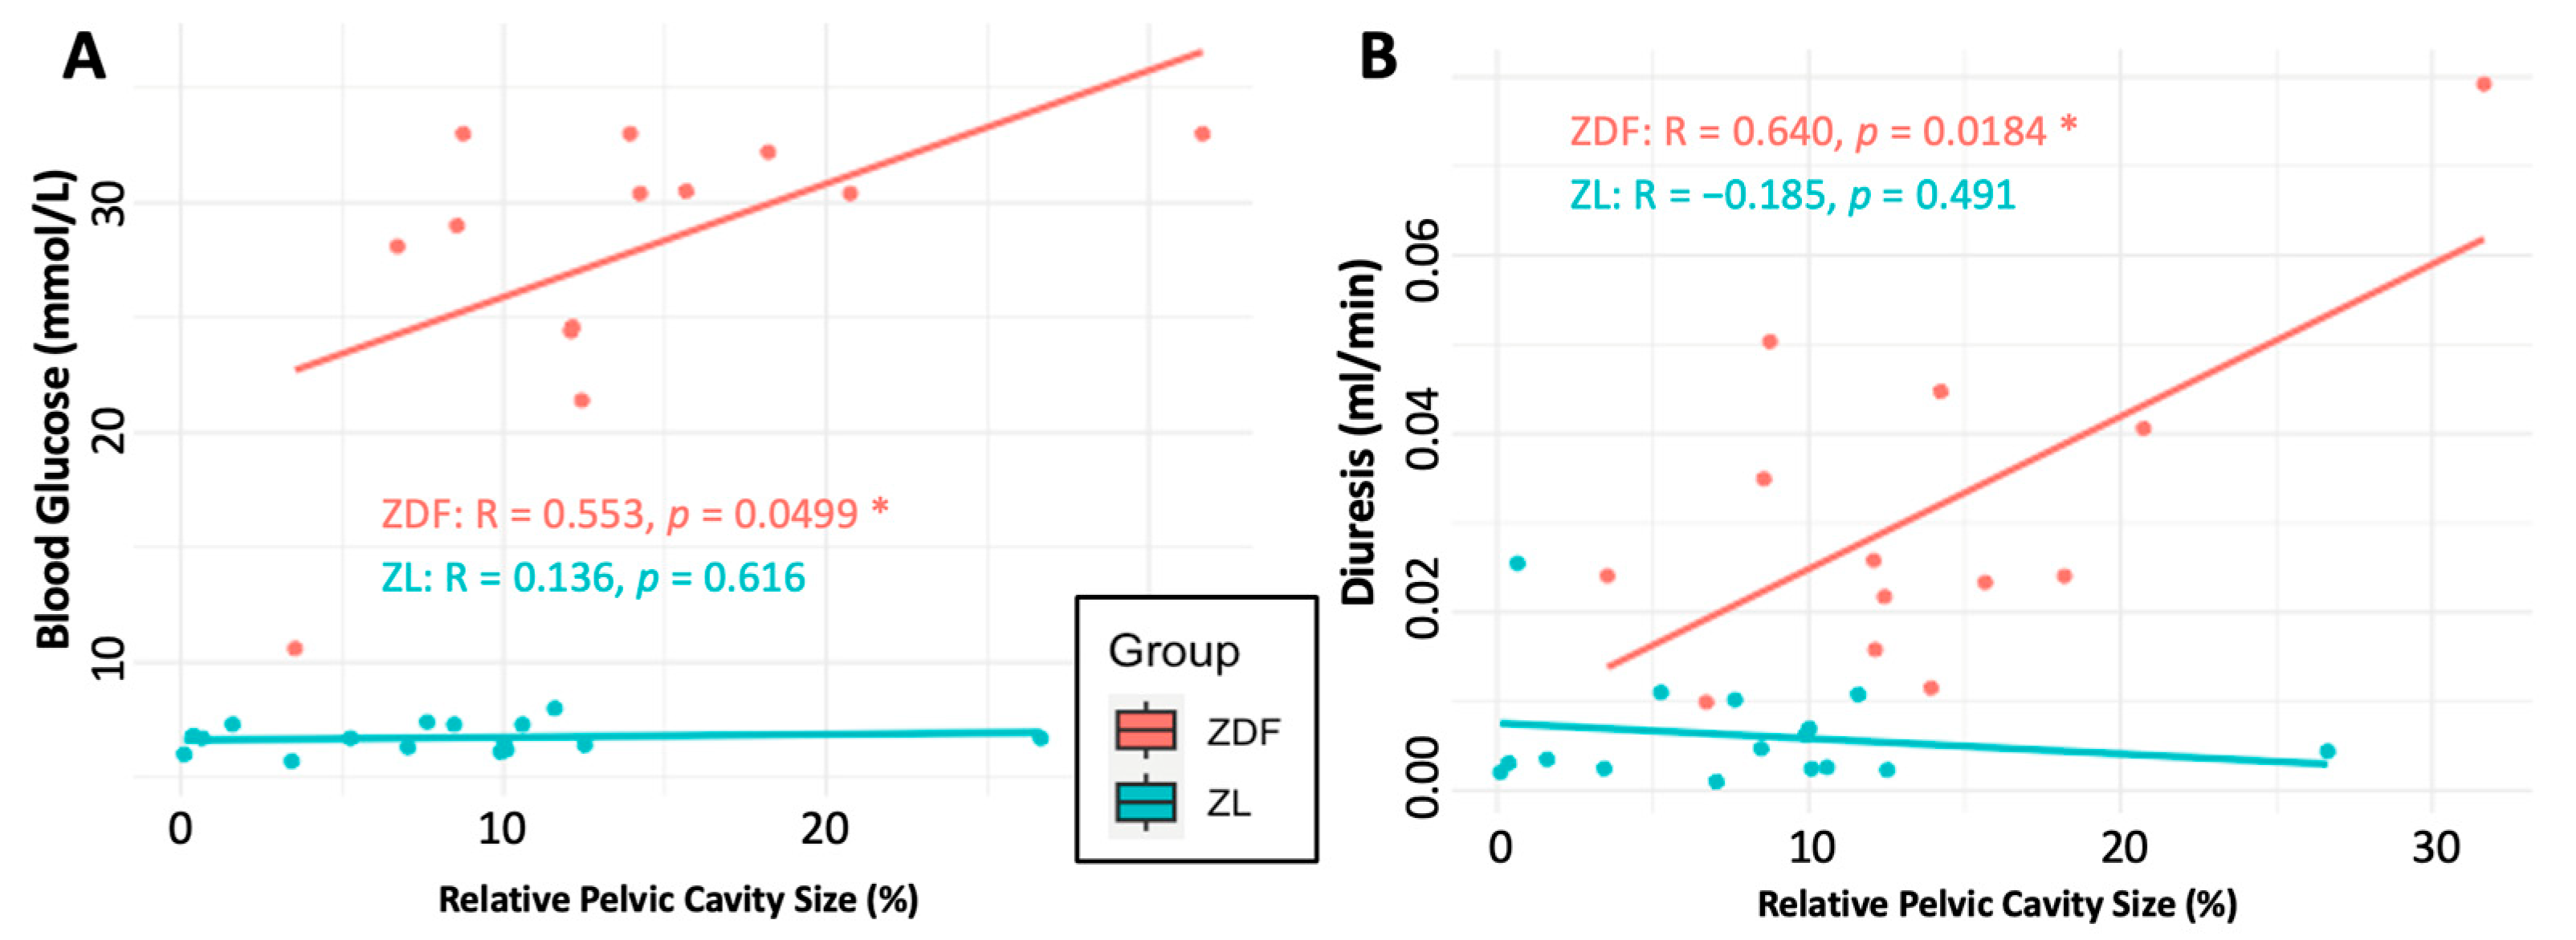

3.4.3. Renal Functional Parameters

4.1. The Effects of Hydronephrosis on Healthy (ZL) Rats

4.2. Implications for Diabetes and DKD Research